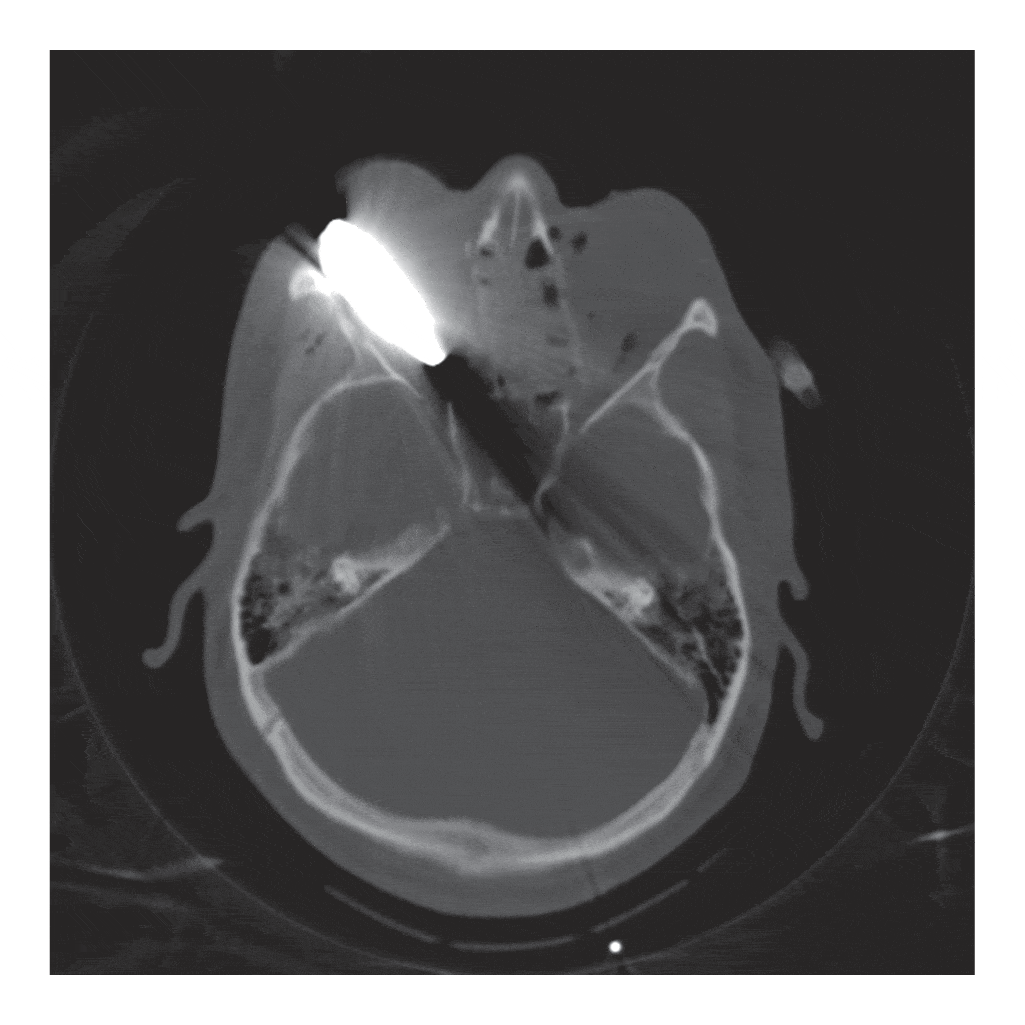

KID Gets Airsoft BB To The Eye! (GETS STUCK) YouTube Gel Blaster Eye Injury To examine the clinical characteristics of patients who have experienced blunt ocular injuries from “orbeez” hydrated gel pellets (spin master corp.), and to. Gel blasters, which shoot soft gel pellets, may seem harmless, but they can cause significant eye injuries if the pellets hit the eye. This series demonstrated that ocular injury resulting from gel pellet projectiles can result in. Gel Blaster Eye Injury.